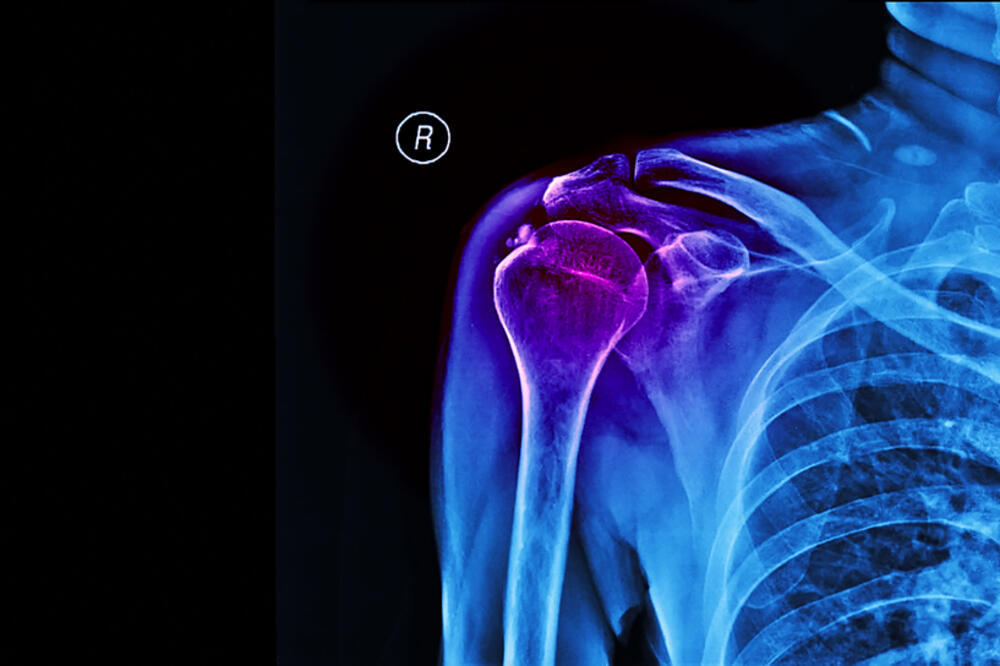

Radiolozi se često susrijeću sa naslagama kalcijuma u ​​zglobovima i tetivama svojih pacijenata. Ali, zbog specifičnosti lokacije, nije uvijek lako razlikovati kalcifikacije na snimku od okoštavanja vezivnog tkiva ili stranog tijela. Kalcifikacija zglobova je sve češće stanje.

Simptomi kalcifikacije tetiva su prilično jasni: pacijenti se često žale na "štipanje", osjećaj da je nešto zaglavljeno u tijelu i ne dozvoljava da se ekstremitet savije ili ispravi do kraja. Ponekad je bolno, ponekad stvara ograničenu pokretljivost. Obično su pogođene tetive u ramenima, ali ponekad su pogođeni ligamenti u laktovima, kukovima i rukama.